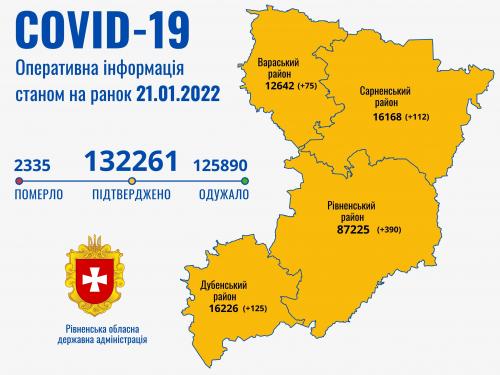

Коронавірус повертається: як стрімко зростає кількість хворих на Рівненщині (ВІДЕО)

Пів тисячі - у важкому стані, 9 жителів Рівненщини померли за добу від коронавірусу